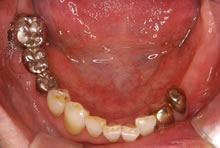

【1】初診時 左下の歯がない状態